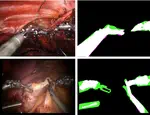

We have recently published the paper “Garcia-Peraza-Herrera, L. C., Fidon, L., DEttorre, C. Stoyanov, D., Vercauteren, T., Ourselin, S. (2021). Image Compositing for Segmentation of Surgical Tools without Manual Annotations. Transactions in Medical Imaging (📖)”. Inspired by special effects, we introduce a novel deep-learning method to segment surgical instruments in endoscopic images.